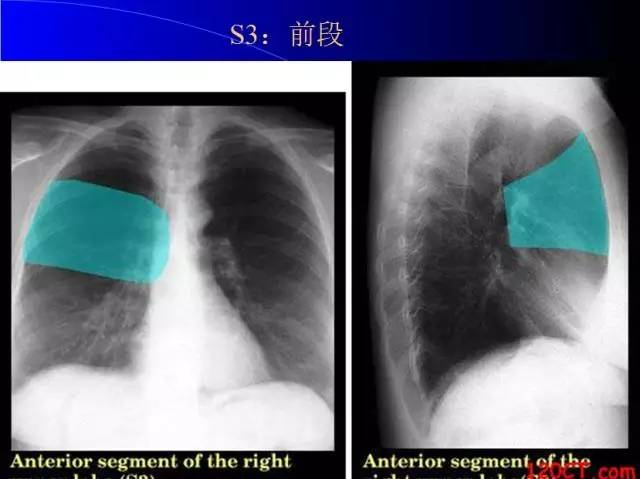

肺部基础X片及CT片解读